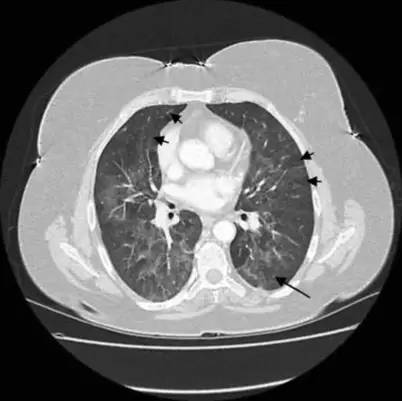

急性期胸部CT表现为两肺弥漫的磨玻璃密度影或广泛的实变影,主要分布在中下肺(如图7)。

图 7:OHP急性期胸部CT表现

慢性期胸部CT表现为:两肺内不规则的线样、网状、或蜂窝状阴影结节影,靠近胸膜分布局部有磨玻璃样改变,并可见牵张性支气管扩张(图8)。

图 8: OHP慢性期胸部CT表现